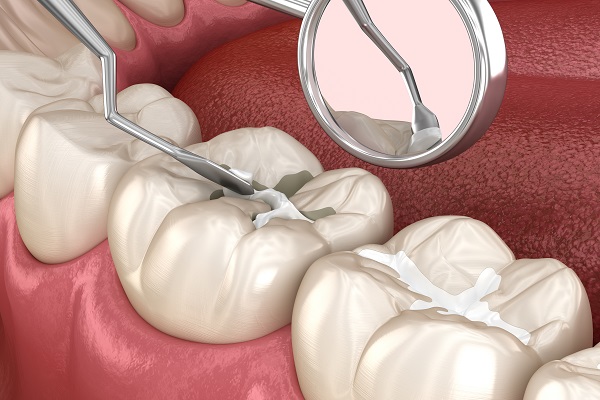

Dental Cleanings &

Exams

Professional teeth scaling, polishing, and comprehensive oral checkups to remove plaque and catch early signs of decay or gum disease.